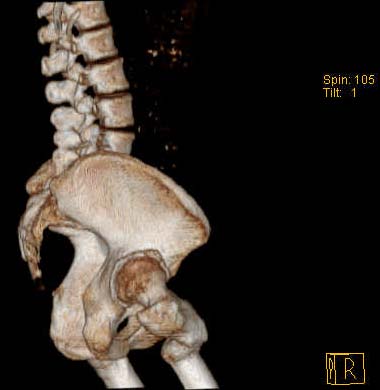

Уважаемые коллеги!Женщина, 35 летВ прошлом по поводу врожденного вывиха бедра перенесла операцию остеотомии по Шанцу

с удлинением правой ноги за счет бедра на уровне диафиза. В последнее время прогрессируют боли в правом тазобедренном суставе, порочное положение правой ноги, затруднена ходьба.Вопросы:1) Целесообразно ли эндопротезирование правого тазобедренного сустава?2) Целесообразный ли следующие действия: канал бедренной кости предполагаем вскрыть для введения ножки протеза на высоте угловой деформации, предполагаем низведение большого вертела с мышцами; протез будет подобран индивидуально, предполагается умеренная версия?В приложении рентгенограммы и трехмерная КТ.В цветном и более качественном варианте КТ размещена здесь

Похожий случай представляем на ретгенограммах. Операция выполнена в 1996 г.